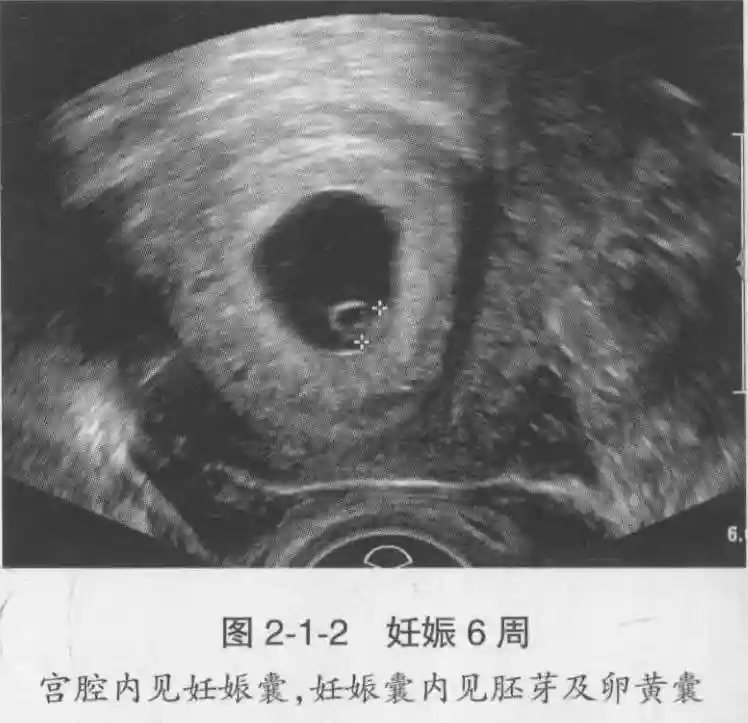

1️⃣妊娠囊:早期妊娠囊:正常妊娠囊位于宫腔上段,表现为宫腔内圆形或椭圆形的无回声区,周边为完整的、厚度均匀的强回声环,强回声环厚度≥2mm,强回声是妊娠绒毛的回声,随着妊娠囊的增大,形成特征性的“双环征” ,10周以后消失。正常的妊娠囊增长速度是平均 1 mm /d。

2️⃣卵黄囊:是妊娠囊内第一个解剖结构,直径<7mm。表现为小环状,中央为无回声,囊壁薄,内透声好。卵黄囊位于胚胎旁胚外体腔内。卵黄囊通常在孕5-6周时出现,5-10周稳步增长,一般不超过7mm,至12周消失。妊娠囊的大小与卵黄囊之间有一定关系,妊娠囊平均直径> 8 mm 时,经阴道超声均应显示卵黄囊,妊娠囊平均直径> 18 mm 时,经腹超声均应显示卵黄囊。

3️⃣胚胎:胚胎通常在6-7周时可以为超声显示,起初为胎芽,表现为卵黄囊一侧局部组织增厚,达到1 -2 mm 时才有可能为超声测量出来。达4-5mm时可见胎心搏动,相应孕周为6-6.5周,妊娠囊大小为13-18mm。胚芽长度≥7㎜时仍未见心管搏动,提示胚胎停止发育。胚胎的出现和妊娠囊直径的关系:妊娠囊直径> 16 mm 时,经阴道超声应显示胚胎。妊娠囊直径> 25 mm 时,经腹超声均应显示胚胎。